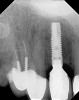

Figure 18  (Case 2) New implant in place 6 months after graft.

Figure 18

Figure 23  (Case 2) Radiograph at 24 months post loading.

Figure 23

A 53-year-old woman presented with a failing implant in the No. 7 site (Figure 12 and Figure 13). Her desire was to eliminate infection and preserve esthetics. A team effort between the periodontist and restorative dentist to advocate for additional restorative dentistry as well as manage the patient’s expectation of time required was essential. In addition, the patient needed to have realistic expectations of a compromised outcome. Both the restorative dentist and the periodontist informed the patient about the difficulty of achieving this with acceptable esthetic results. Mutual emotional and technical support was required to successfully complete this case, from initial grafting of the defect to placement of anterior restorations (Figure 14 through Figure 23).